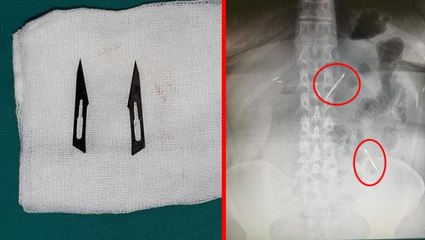

Manisa'da gaz sancısı ve karın ağrısı şikayeti ile hastaneye giden Mustafa Barutçuoğlu'nun (23) safra kesesinden, ameliyatla 400 tane taş çıkarıldı. Genel Cerrahi Uzmanı Dr. Nalbant, ameliyatı yapmaktan değil taşları saymaktan yorulduğunu söyledi.